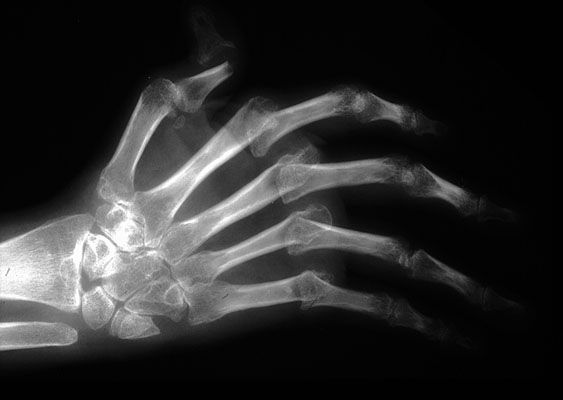

Rheumatoid arthritis (RA), hand, X-ray

Radiograph of a hand in late-stage rheumatoid arthritis showing subluxation of the metacarpo-phalangeal joints and ulnar deviation of the fingers, x-ray.